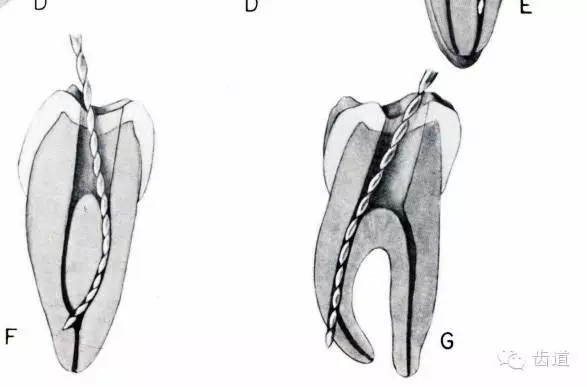

熟悉根管解剖形態(tài);X線應(yīng)能清楚顯示根管和根尖區(qū);及時換銼;預(yù)彎根管銼;小號銼應(yīng)做充分預(yù)備(08#---20#);達(dá)到工作長度時不能做旋轉(zhuǎn)預(yù)備;使用H銼前應(yīng)先使用同號的K銼預(yù)備;換大一號銼之前,該銼應(yīng)能在根管內(nèi)自由出入;細(xì)小的彎曲根管應(yīng)盡量使用小號銼充分預(yù)備,避免堅(jiān)硬的大好銼;向彎曲相反方向預(yù)備。

原因:根管銼無預(yù)彎,換銼過快,跳號。

預(yù)防臺階形成:細(xì)小,彎曲,鈣化根管的預(yù)備時,準(zhǔn)確工作長度,髓腔內(nèi)充滿NaClO預(yù)彎06#,08#10#根管銼,逐漸達(dá)到工作長度,采用逐步根管銼預(yù)備法,1-3mm短程提拉。

早發(fā)現(xiàn)臺階可去除,25#或30#銼產(chǎn)生的臺階去除較困難。方法同通過根管堵塞物。